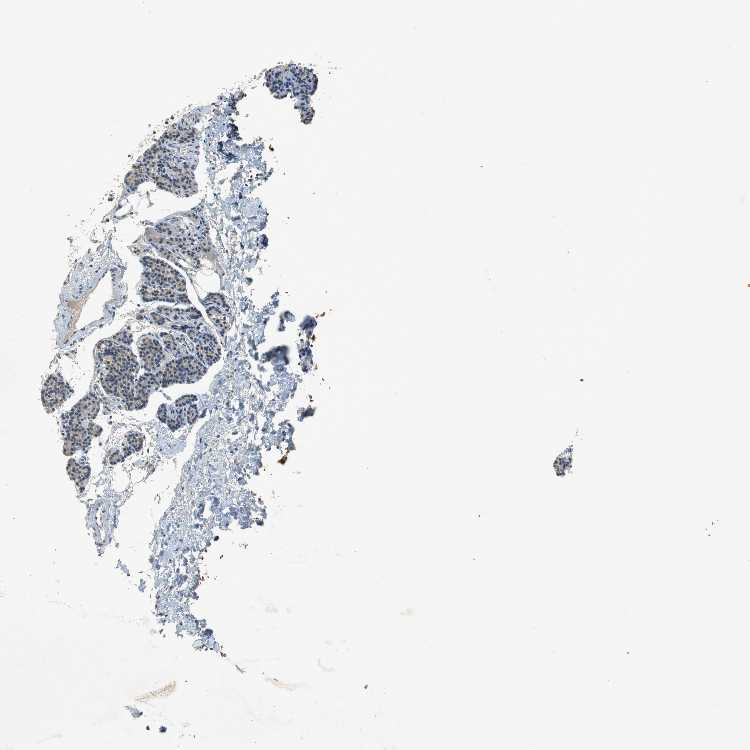

TISSUE PRIMARY DATA PARATHYROID GLAND Show tissue menu

PARATHYROID GLAND - Antibody stainingi

Antibody staining in the annotated cell types in the current human tissue is reported as not detected, low, medium, or high, based on conventional immunohistochemistry profiling in selected tissues. This score is based on the combination of the staining intensity and fraction of stained cells.

Each image is clickable and will lead to virtual microscopy that enables deeper exploration of all samples and also displays staining intensity scores, fraction scores and subcellular localization as well as patient and tissue information for each sample.

Antibody HPA001674Antibody HPA005987

Glandular cells MediumLow